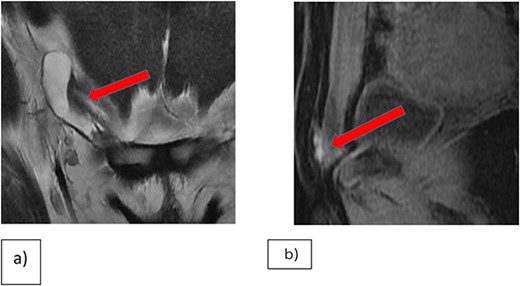

Enhanced CT-scans of the abdomen and pelvis demonstrated an increase in the size of the elongated cystic lesion. A multiplanar multi-sequential MRI of the pelvis revealed a right inguinal lesion, likely an endometrial plaque with hydrocele of the canal of Nuck (Fig. 1).

(a) Coronal T2WI showing right inguinal tubular cystic lesion that is communicating with peritoneum highly suggestive of communicating hydrocele of canal of Nuck. (b) MRI Sagittal T1 fat saturation, demonstrating that the medial superior aspect of the cyst is bright on T1WI in keeping with hemorrhagic contents versus endometrial implant.